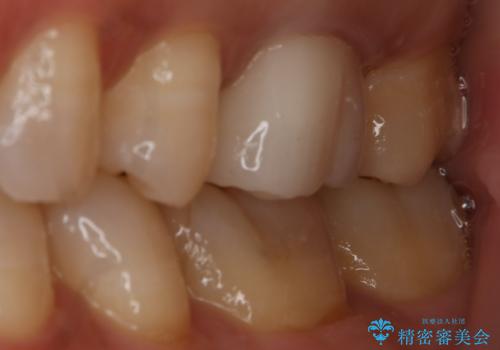

銀歯を白くしたい セラミックインレー

- 左上7番の銀歯をセラミックにやり変え希望の患者様です。

切削量・形態からセラミックインレーでの治療を計画しました。

銀歯とその直下のう蝕を除去した後、CRにて裏層しています。

インレー装着の際はラバーダムを使用しています。